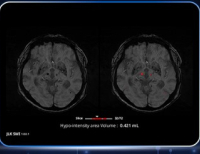

- 제이엘케이, 磁化강조 뇌 MRI 영상 기반 AI ‘JLK-SWI’ 日 허가 … 작은 출혈 정밀진단, 미‧일 동시 허가 통산 7 품목

- 의료 인공지능(AI) 전문기업 제이엘케이는 자사의 뇌 자화(磁化)강조 자기공명영상(MRI) 기반, 즉 SWI(Susceptibility Weighted Imaging) 기반 AI 분석 솔루션이 일본 의약...

- 2025-09-30